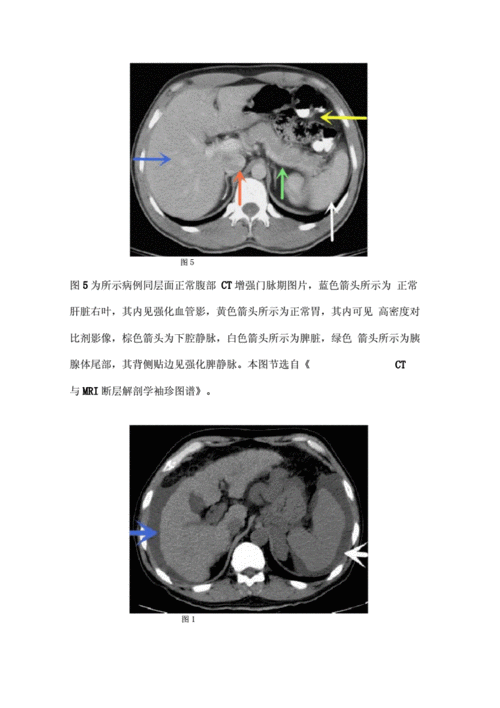

医生文章 正文 肝硬化主要ct表现: 1.

肝癌ct表现

肝硬化CT